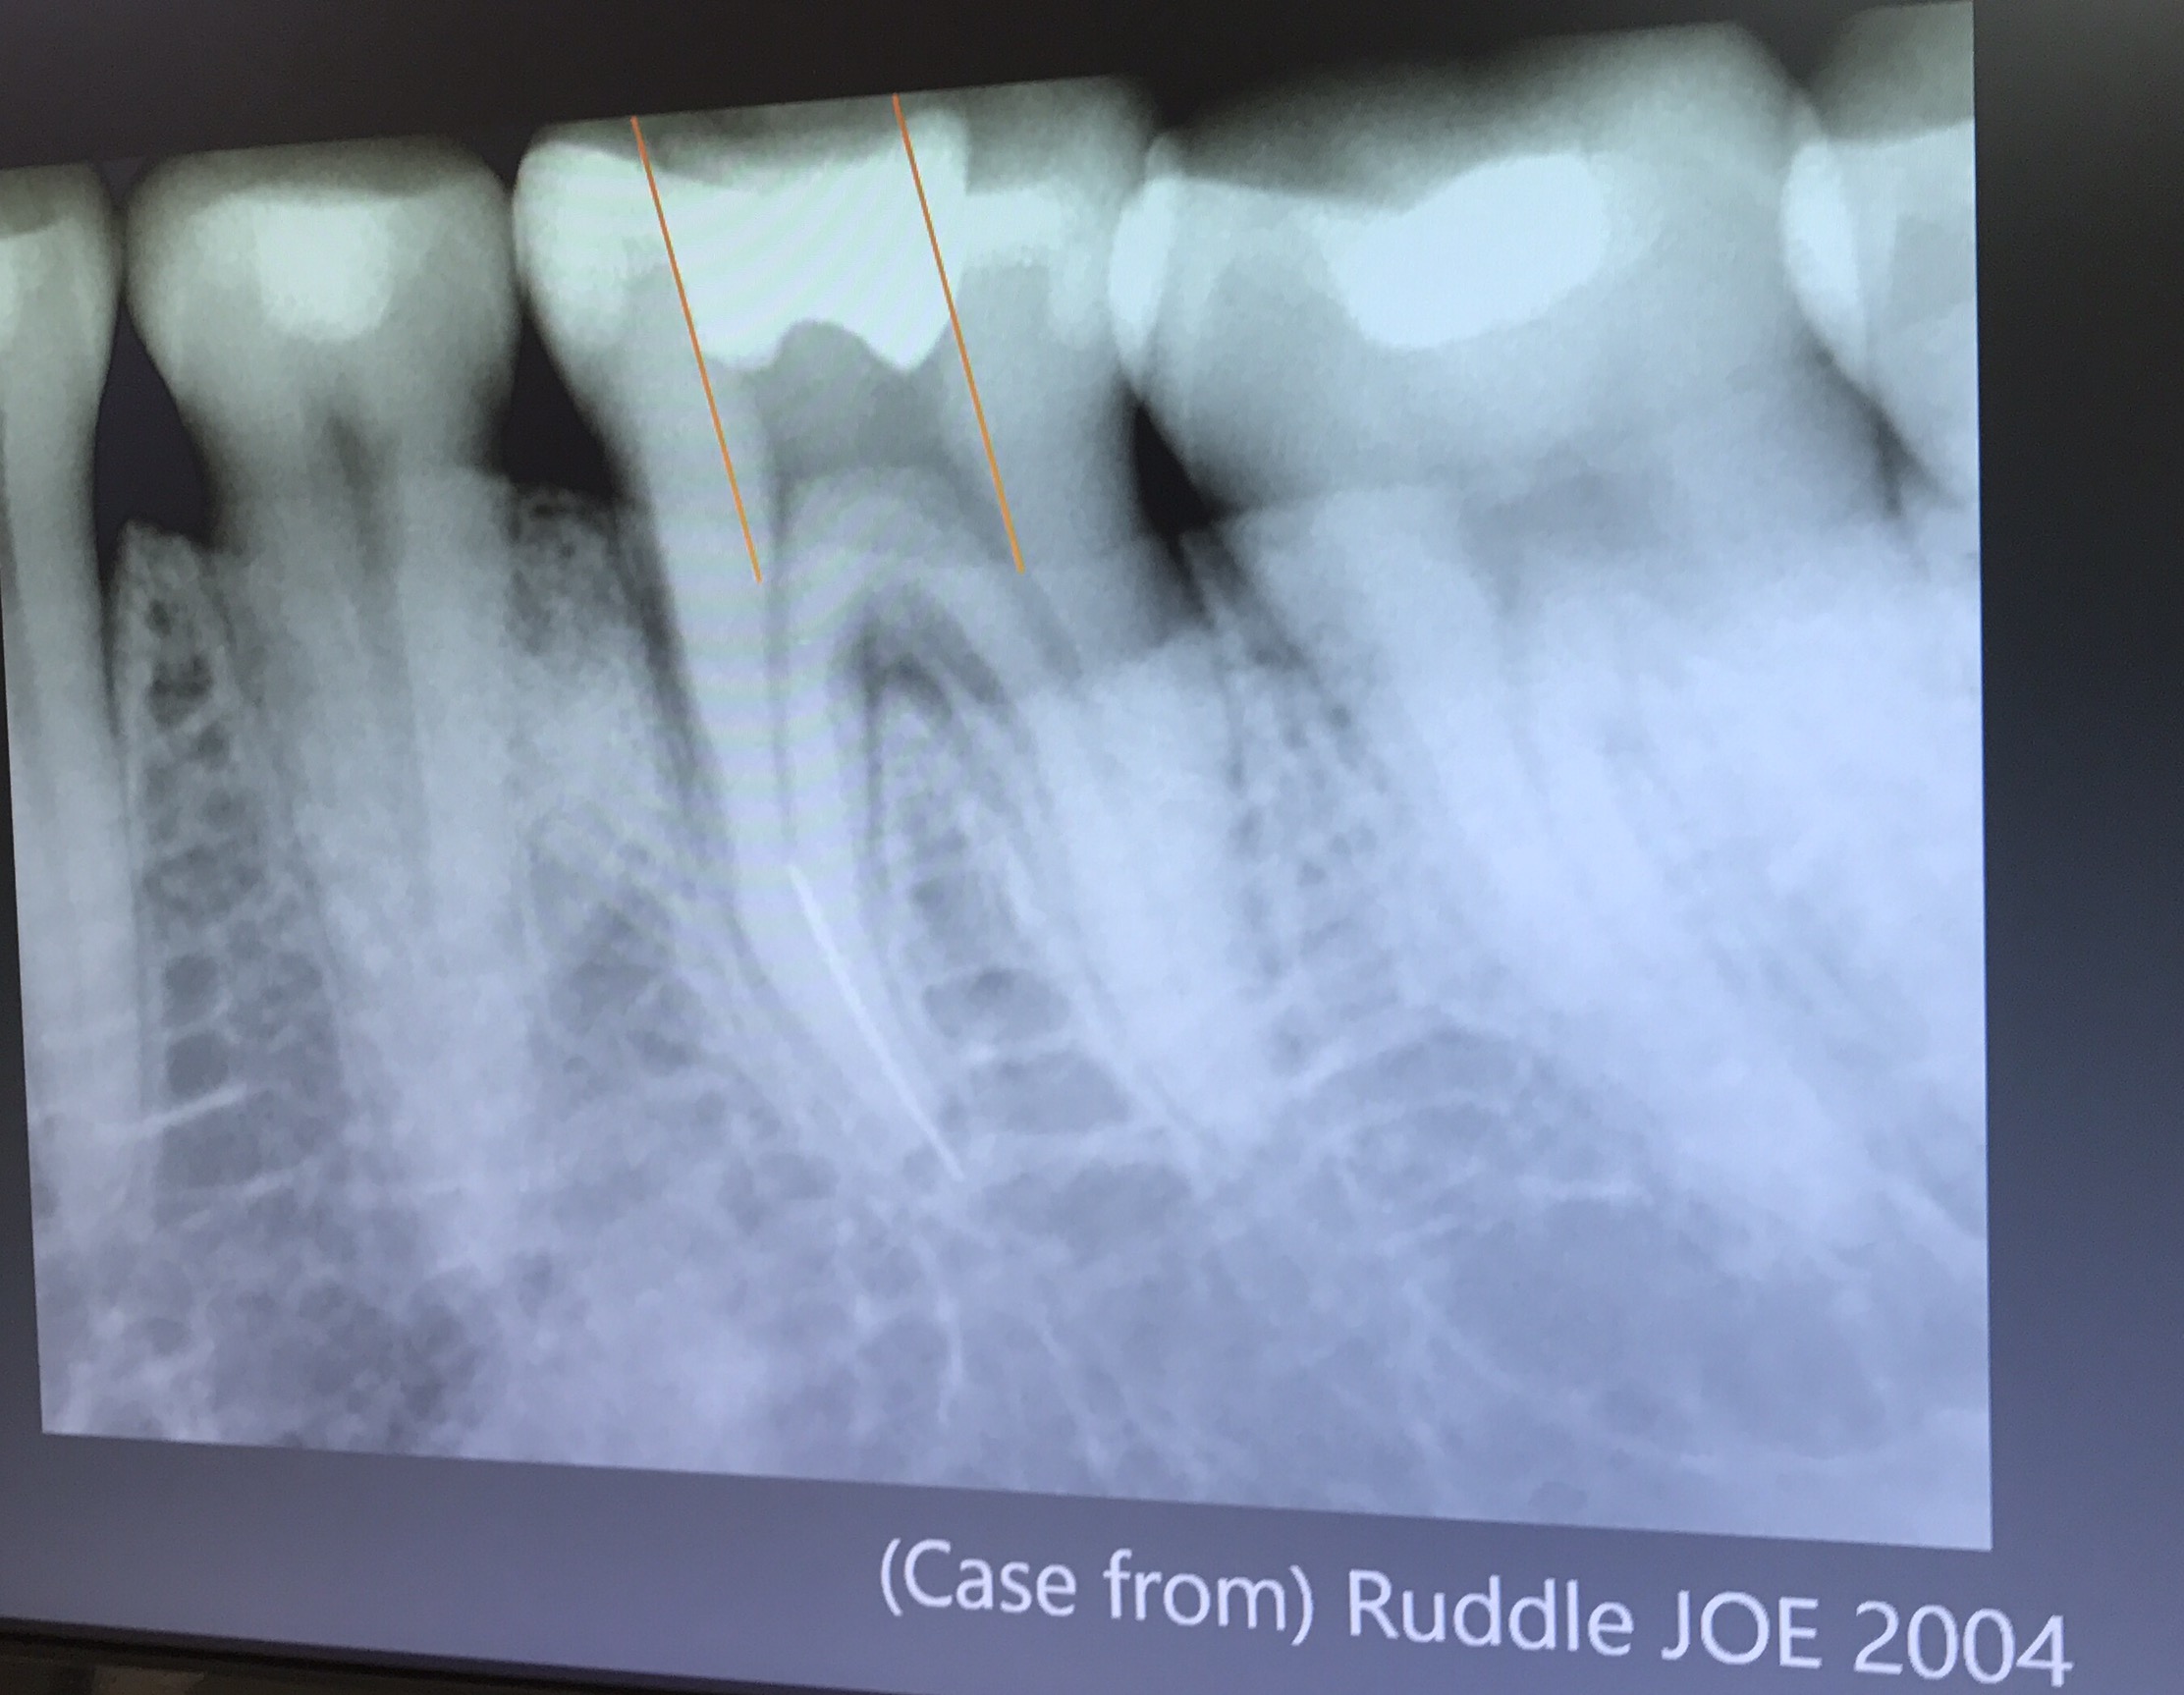

การทำ Platform staging คือการทำให้เกิด Straight access ครับ

แนวเส้นสีแดง คือ Coronal access

การเคลื่อนของเครื่องมือในทิศทวนเข็มนาฬิกา

ในสมัยก่อน การทำ Staging platform ใช้ Gates glidden drill

แสดงการเกิด space รอบๆ เครื่องมือที่หัก จากปลาย tip ของ ET20 ทำให้เกิด small groove